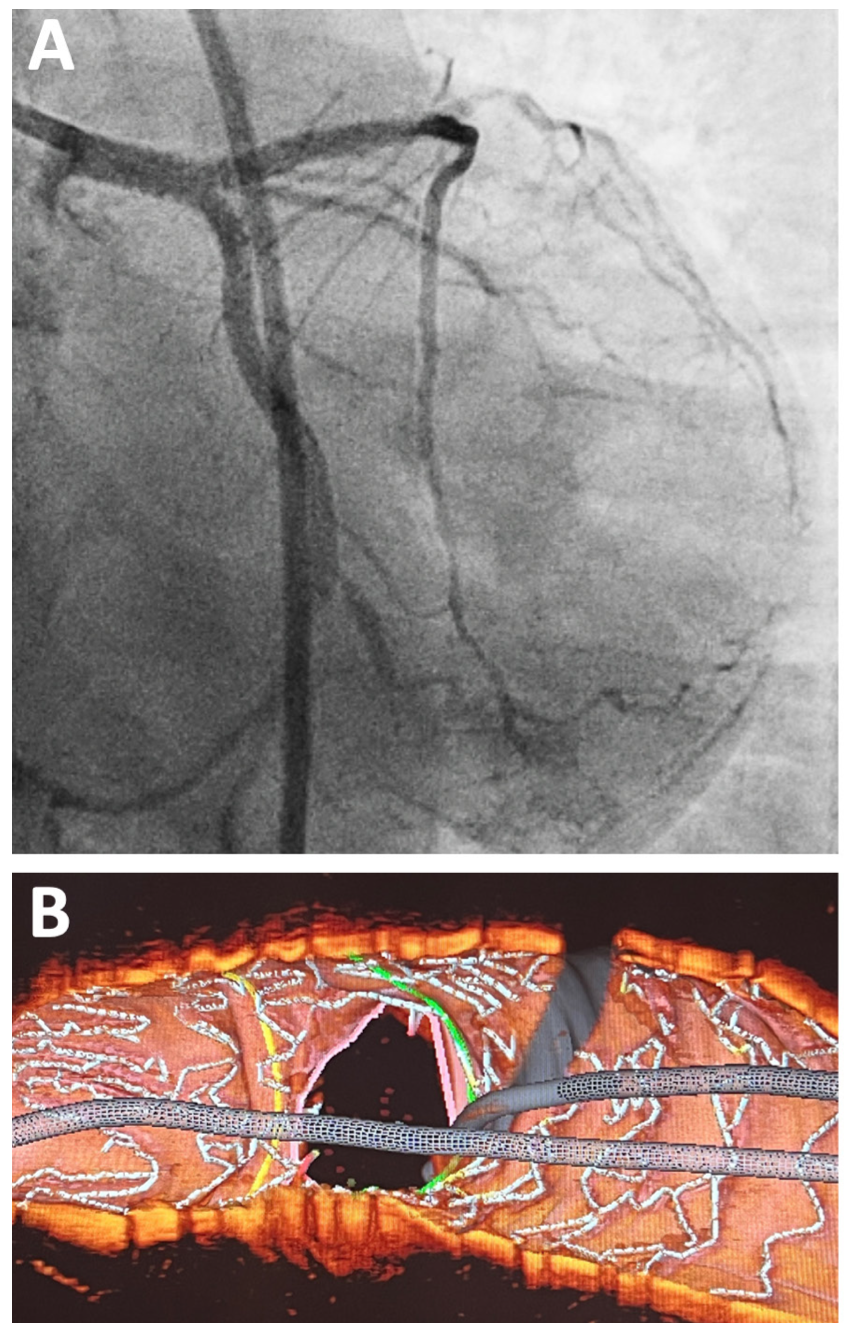

A 53-year-old man was planned for staged percutaneous coronary intervention (PCI) to the left circumflex artery (LCX). He had history of primary PCI at the proximal left anterior descending (LAD) 6 months earlier. Following coronary angiogram (Figure 1A, 1B), it was decided to perform an initial optical coherence tomography (OCT) evaluation. However, during delivery to the LAD, the OCT catheter was railed-off from the guidewire and knocked to the ostial LCX (Figure 2A and Video 1).

Guide-catheter repositioning was performed to have a more coaxial engagement. Subsequently, the OCT catheter was successfully delivered to the distal LAD. The OCT study revealed stenosis with fibrotic plaque at the ostial LAD, eccentric lesion at the distal left main (LM), and intimal tear at the ostial LCX (Figure 3). During OCT evaluation, the patient was experiencing chest pain with unstable hemodynamics. Careful contrast injection revealed dissection at the ostial-proximal part of LCX with compromised antegrade flow (Figure 2B). We performed double-kissing culotte stenting at the left main bifurcation. The patient was then stabilized. The final angiogram and 3-dimensional OCT showed good results (Figure 4).